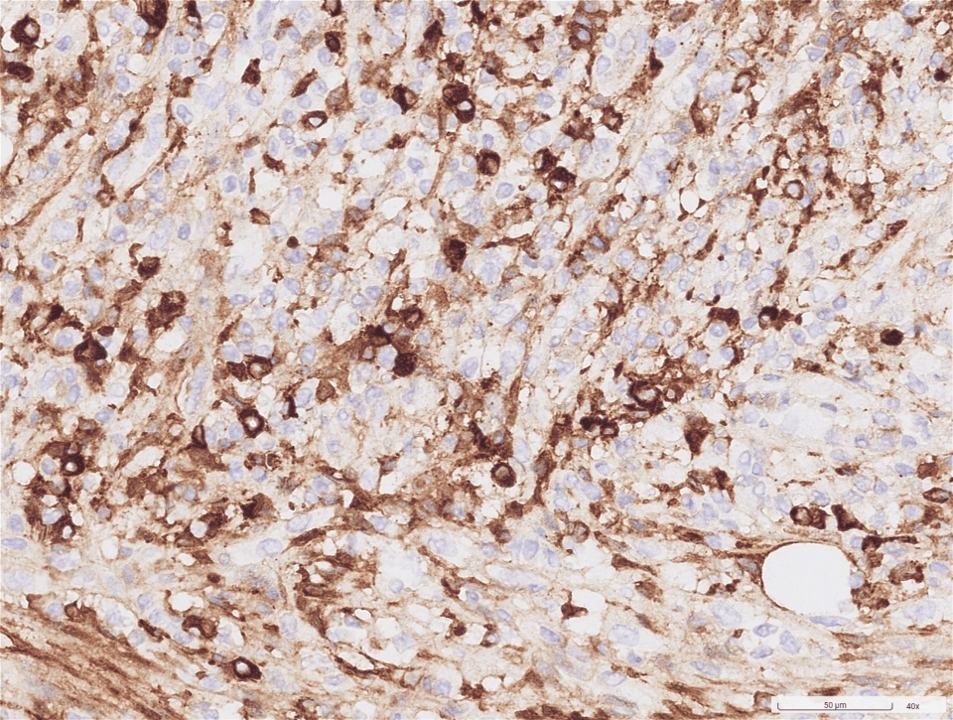

出院後約1-2個禮拜,病患因右上腹痛再度來急診,第三次住院由簡榮南副院長primary care。電腦斷層顯示腹膜炎(尤其是右上腹)、雙側肋膜積液及膽囊壁增厚。病患住院期間再次接收左臉頰切片,但結果仍是沒有發現惡性腫瘤。簡副認為,一個這麼大的腫瘤,連續多次切片都沒有發現是惡性,那應該要往其他方向去思考。因此在查閱過相關資料後,當科PGY學妹許昕瑜醫師抽了IgG、IgG4及檢驗可能造成頭頸部腫大的病毒、黴菌感染(包含EBV, aspergillus等),結果意外發現IgG、IgG4 上升,也因此懷疑到IgG4 related disease。會診風濕免疫科時,當時根據放射科報告,認為有骨頭侵犯等較惡性的表現,比較不像IgG4 related disease。然而最後還是有請病理科染IgG, IgG4, 也發現有符合IgG4 related disease的病理診斷,包含淋巴球及漿細胞浸潤合併纖維化,IgG4:IgG陽性細胞比>40%及IgG4陽性細胞> 10/HPF。同時,病患合併一個以上器官的腫大或腫塊,以及血清IgG4>135mg/dL,藉此確診IgG4 related disease,也給予病患臉頰腫、腹痛(IgG4相關性自體免疫肝炎、膽管炎及腹膜炎)及肋膜積水一個合理的解釋。病患也開始接受類固醇治療,牙關緊閉及左臉腫的症狀也在治療後明顯改善,肝功能的各項指數也逐漸恢復正常。